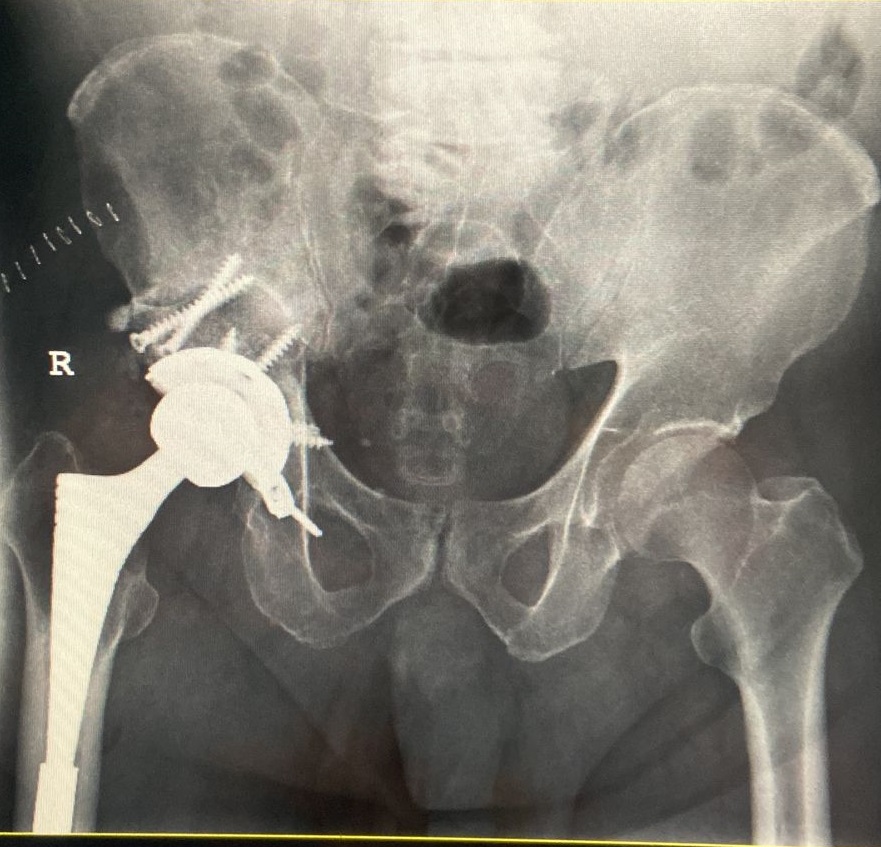

71-year old male with a right total hip following fracture dislocation 21 years ago presents with a 6 month history of increasing pain and shortening of the right lower limb. Recommended for acetabulum revision. Performed with graft multi hole revision cup and change of femoral head to 36 mm